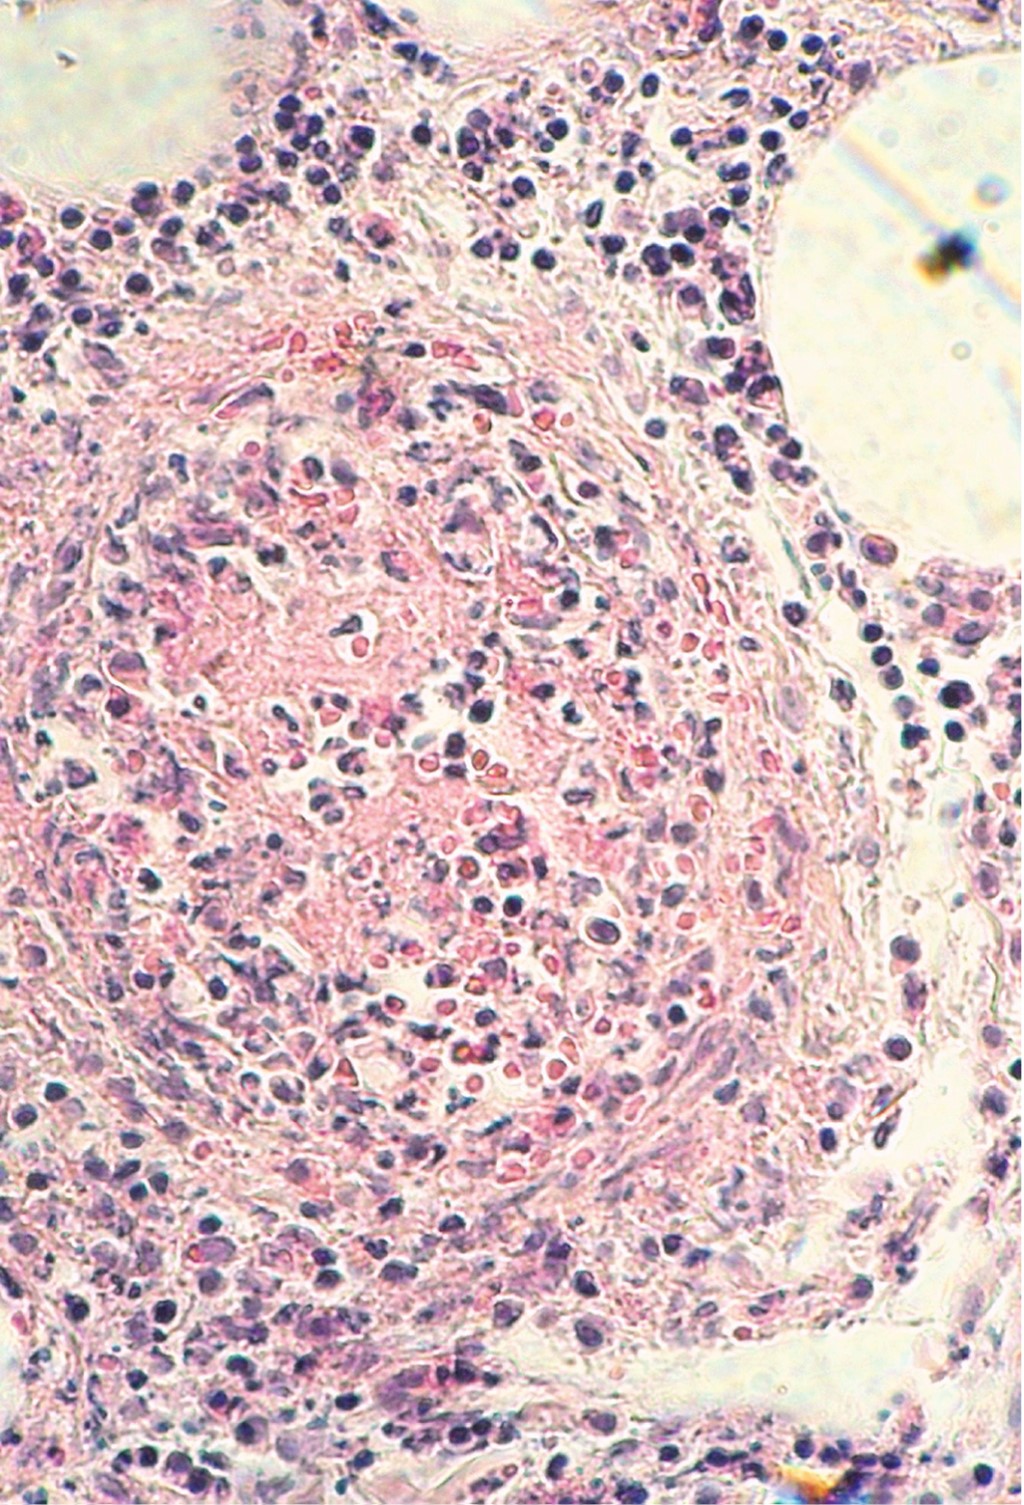

Cutaneous polyarteritis nodosa: presentation of two cases and literature review

Cutaneous polyarteritis nodosa is a form of vasculitis that affects small to medium sized arteries, with unknown incidence due to a low frequency. The exact etiopathogenesis is unknown. Clinically, it is characterized by painful subcutaneous nodules associated to livedo reticularis, that frequently evolves to ulcers on lower extremities, with a chronic and relapsing clinical course. Generally, it only involves skin, however, extracutaneous manifestation has been reported. In this article we describe different clinical presentation and management of two patients with different gender and age.

Figure 1